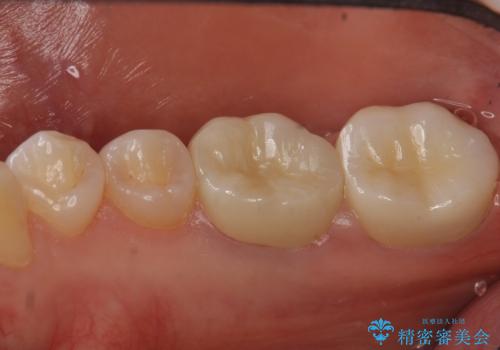

変色した樹脂の詰め物 セラミックでのやり替え

奥歯が樹脂の詰め物で継ぎ接ぎになっていることが確認されたため、今後の虫歯リスクを減らすために適合の良いフルジルコニアクラウンを入れていきます。

樹脂で継ぎ接ぎになった歯はそうでない歯と比べて虫歯になるリスクが高いです。

樹脂をすべて取り、虫歯も取り切った後に適合の良いクラウンを装着することで今後の虫歯リスクを減らすことができます。